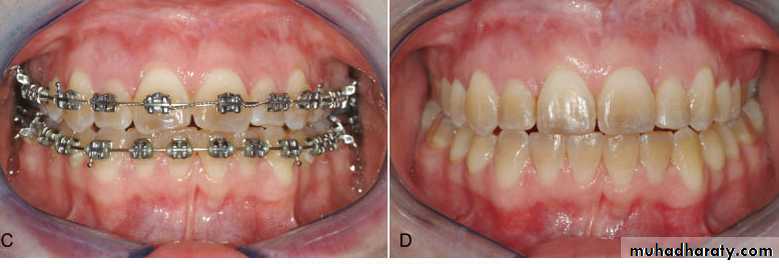

In all patients whether children or adolescents, the crossbite should be overcorrected so that the palatal cusps of upper teeth occlude on the lingual inclines of buccal cusps of lower molars.

After active treatment the appliance is left passively in place for 3 months.

A removable retainer that covers the palate is needed to prevent relapse for 6 months or more.

The crossbite should be slightly overcorrected so that the palatal cusps of upper teeth occlude on the lingual inclines of buccal cusps of lower molars.

overcorrection

After retention